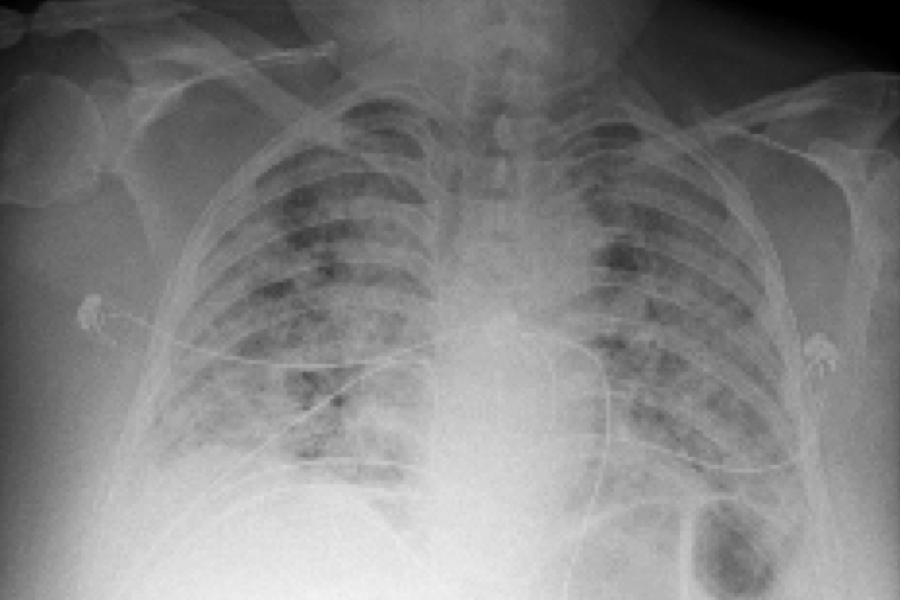

AI Tool Uses Chest X-Rays to Identify Worst COVID-19 Cases